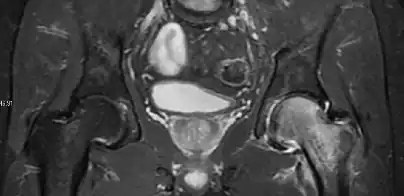

In adults, MRI is currently playing a definite role in the assessment of osteoarthritis. Although traditionally belonging to the arena of radiographs, the role of MRI has been stressed after the term femoral acetabular impingement was coined in 2003. Growing interest has been focused in accurate diagnosis of the acetabular and femoral morphological abnormalities that may lead to early osteoarthritis.[1]

MR imaging is considered paramount to these objectives, mainly when surgery is considered, due to the ability of MRI to portray the whole section of the femoral neck surface, as well as to image the labrum and articular cartilage.[1]

Diagnosis of impingement can only be achieved if, besides imaging findings, there are also clinical symptoms and positive impingement maneuvers.[1]

Most of the angles and measurements described in the plain radiograph section can be accurately reproduced on MRI. In addition, the superiority of MRI resolution with intra-articular contrast allows detection of labral and chondral abnormalities that may influence the choice of medical, percutaneous, or surgical management (Figure 9).[1]

Figure 9:

-

Sagittal T1 weighted image showing anterosuperior labral tear.[1] -

Sagittal T1 weighted image showing chondral lesion.[1] -

Sagittal CT-arthrography showing posteroinferior chondral injury.[1] -

Coronal CT-arthrography (d) showing ligamentum teres tear.[1]

MR arthrography has proven superior in accuracy when compared to native MR imaging. It is considered the best technique to assess the labrum. Knowledge of the normal variable morphology of the labrum helps to differentiate tears from normal variants. A triangular shape is most commonly seen in 66% of asymptomatic volunteers, but round, flattened, and absent labra can also be found in asymptomatic populations. MR arthrography has demonstrated sensitivity over 90% and specificity close to 100% in detecting labral tears. Loose bodies are demonstrated as filling defects surrounded by the hyperintense gadolinium.[1]

Association between labral tears and chondral damage has been demonstrated. This underscores the interaction between cartilage and labrum damage in the progression of osteoarthritis. Chondral damage to the posteroinferior part of the acetabulum as a contrecoup lesion occurs in approximately one-third of pincer cases secondary to persistent abutment on the anterior part of the joint leading to a slight posteroinferior subluxation. This is considered a bad prognosis sign.[1]

MR arthrography can also demonstrate ligamentum teres rupture or capsular laxity, which are debated causes of microinstability of the hip. Elongation of the capsule or injury to the iliofemoral ligament or labrum may be secondary to microtrauma in athletes. MR can demonstrate abnormalities in these cases, such as increased joint volume or a ligamentum teres tear (Figure 9).[1]